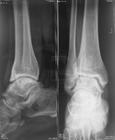

惠普爾病關節2.關節 2/3 以上病人有關節炎。關節炎的特徵為間歇性、遊走性,有時持續僅1~4 周,大、小關節均可累及。受累關節表現疼痛、紅腫及局部發熱。關節炎發作以多關節炎為常見,偶有單關節發作。最常受累的關節是腕關節、膝關節,其次為掌指關節、掌跖關節、踝關節、脊柱關節、髖關節、肩關節、肘關節。少數病人可發生強直性脊柱炎,表現為下背部疼痛或脊柱運動受限。

4.免疫學檢查 可有IgG、IgM、IgA 下降,E-玫瑰花結形成數降低,淋巴母細胞轉化率下降,類風濕因子陰性,LE 細胞陰性,抗核抗體陰性。其他輔助檢查:X 線表現:胃腸道鋇餐顯示整個小腸黏膜皺襞均呈瀰漫性增厚,尤以十二指腸遠端和近段空腸為最顯著。黏膜皺襞增厚、紊亂,有時呈輕度結節狀或有小的充盈缺損。皺襞增厚程度隨疾病的嚴重程度而有所不同。胸部X 線檢查可見肺部浸潤、胸腔積液和胸膜增厚。骨骼X 線檢查有時可見骶髂關節炎、骨質軟化和骨質疏鬆徵象。